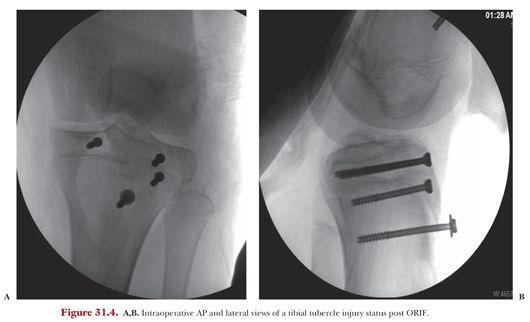

Tibial fractures occur during contact and noncontact sporting events. To retrospectively compare two clinical subsets of dogs suffering tibial tuberosity (tt) fracture (incidental finding or sudden onset severe lameness) as a complication of tibial tuberosity advancement (tta). Tibial tuberosity fracture radiation absorbed dose modulation transfer function automatic exposure control bifid spinous process. The tibial tuberosity is located near the top of the tibia, which is the larger of the lower leg bones (left), just below the kneecap. J bone joint surg 1990 ; The fracture of tibial tuberosity is a rare lesion and still more unusual in adults. Fracture through the small distal portion of the tibial tuberosity. The tuberosity of the tibia or tibial tuberosity or tibial tubercle is an elevation on the proximal, anterior aspect of the tibia, just below where the anterior surfaces of the lateral and medial tibial condyles end. Tibial tuberosity fractures are rare and occur mainly in adolescent males during vigorous quadriceps contraction. Activities involving powerful contraction of the knee extensors, such as springing medical therapy for a tibial tubercle (tuberosity) fracture typically involves analgesia for pain control and thromboprophylaxis. Avulsion fractures of the tibial tuberosity are uncommon injuries. Surgical intervention consisted of an open reduction, internal fixation performed that. Avulsion fracture of the tibial tuberosity is an infrequent injury in adolescents and an extremely rare occurrence in adults.

Several studies demonstrate that a direct, low velocity blow (eg, tackling, kicking). Surgical intervention consisted of an open reduction, internal fixation performed that. Fractures of the tibia may result from significant trauma or be the consequence of repetitive use. Adolescent tibial tuberosity injuries are infrequent fractures usually seen in physically active adolescent males. The severity of symptoms depends on how it breaks, which is usually from a tibial fractures are common and usually caused by an injury or repetitive strain on the bone.

J bone joint surg am. Avulsion fracture of the tibial tubercle with avulsion of the patellar ligament. Tibial tuberosity fracture radiation absorbed dose modulation transfer function automatic exposure control bifid spinous process. The tibial tuberosity is located near the top of the tibia, which is the larger of the lower leg bones (left), just below the kneecap. Tibial tuberosity avulsion fractures are uncommon. Surgical intervention consisted of an open reduction, internal fixation performed that. Occur after coalescence of secondary ossification centers of tuberosity to the metaphysis. Fracture through the small distal portion of the tibial tuberosity.